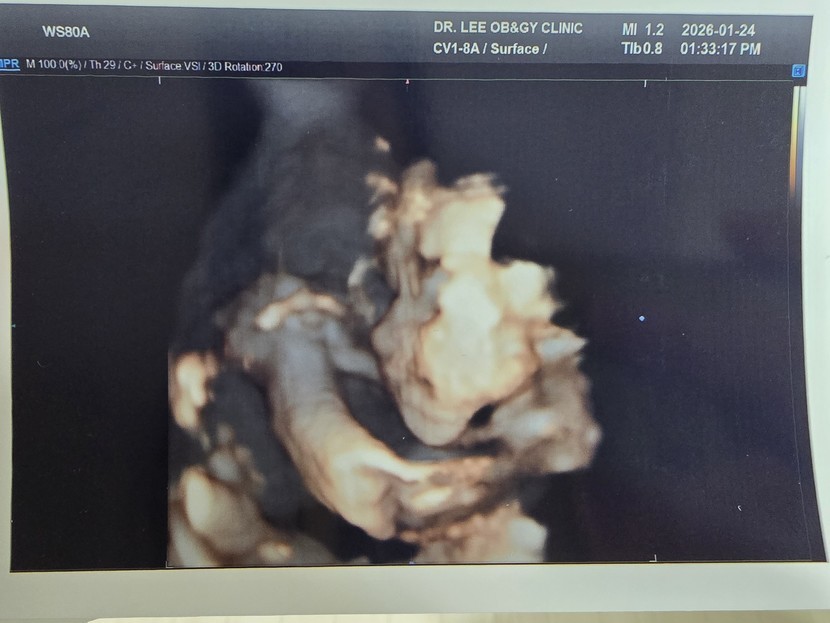

오랜만에 뱃속에 있는 셋째 소식이에요.

어느덧 임신 7개월째네요.

어제 안 사실인데 탯줄 한바퀴가 목에 감겨 있다고!!!

804g으로 잘 자라고 있다고 합니다.